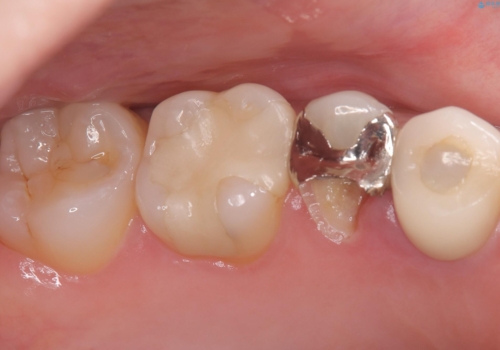

- 主訴:左上真ん中らへんの歯が欠けてしみるので治したい

審美性、適合性の良いセラミックインレーでのやり替えとなりました。

左上4近心に実質欠損を認め、遠心から咬合面にかけてはCR修復が施されていたため、MODインレー窩洞としました。